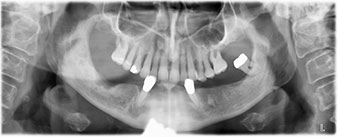

Die 64-jährige Patientin wurde mit einer Unterkiefer-Restbezahnung 38, 33 und 43 und einer klammerbefestigten Interimsprothese im Unterkiefer vorstellig (Abb. 1 und 2).

Zur Planung und Risikominimierung wurde eine dreidimensionale Volumentomografie (DVT, Planmeca) erstellt. Dieses zeigte, dass die Qualität und Quantität des Knochens für eine Operation und Sofortversorgung nach der Fast & Fixed-Methode ausreichend war. Nach Protokoll dieses Konzeptes wird in Regio 35, 32, 42 und 45 implantiert. Durch die bis zu 45-Grad-Schiefstellung der distalen Implantate wird das Durchtrittsprofil nach posterior verlegt und ein größeres Stützpolygon erreicht (Abb. 3).